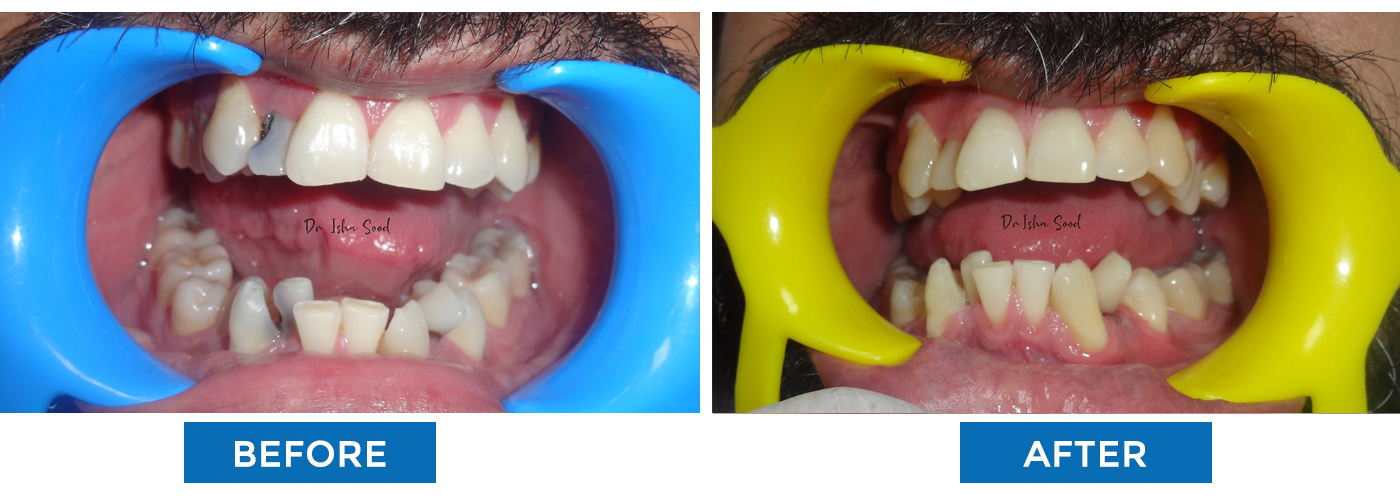

Orthodontic Treatment (Braces)